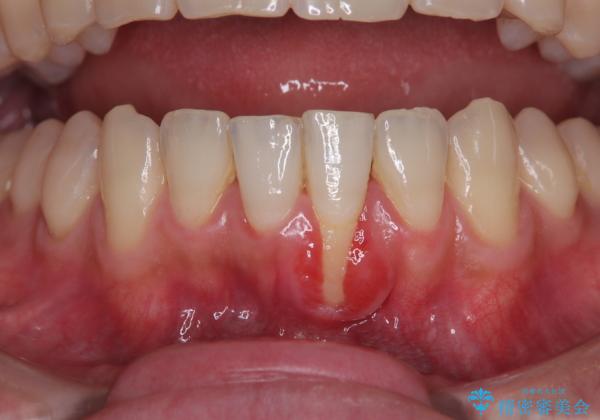

- 他院で矯正治療を終えた結果、下顎前歯の歯肉が退縮してしまい、歯根が見えていることが気になるとのことで来院された患者様です。

一度の処置で十分に根面被覆ができました。

舌側に歯石が溜まりやすく、やや出血が認められるため、定期的なクリーニングが大切となってきます。